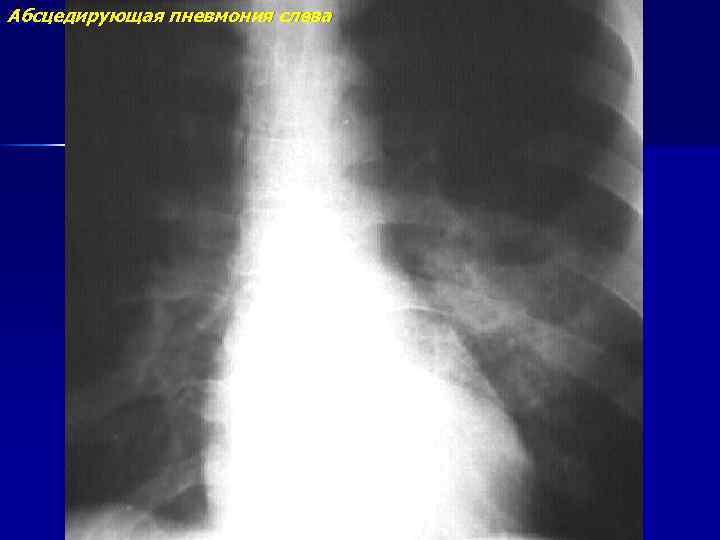

Абсцедирующая пневмония слева